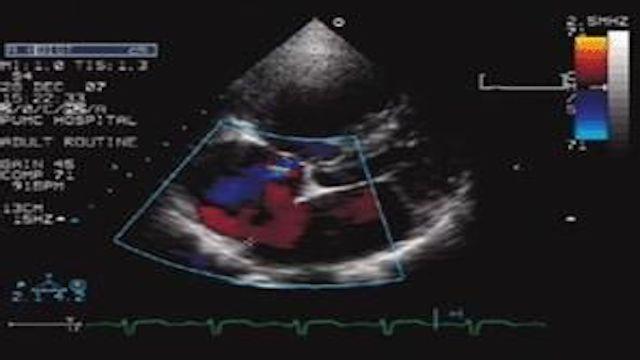

5, échographie cardiaque : l'échographie cardiaque permet d'observer le muscle cardiaque et l'anatomie interne de l'examen ; elle ne peut pas voir directement les artères coronaires, mais en cas d'ischémie ou de nécrose du myocarde, elle affectera le mouvement du myocarde, de manière à répondre indirectement à la situation de l'approvisionnement en sang du cœur ;

7. échocardiographieIl s'agit d'un test non invasif qui examine la structure et la fonction du cœur. L'ischémie ou l'infarctus est déterminé en examinant le mouvement, l'épaisseur, etc. de la paroi ventriculaire. En cas d'ischémie, le mouvement de la paroi ventriculaire est affaibli et non coordonné, et le myocarde infarci est aminci, voire ne bouge pas (se contracte) ou bouge dans la direction opposée (se contracte), ce qui est médicalement connu sous le nom de "tumeur de la paroi ventriculaire", et il peut également y avoir un "thrombus de la paroi attachée". Chez les patients présentant des infarctus importants, la fonction cardiaque mesurée par échographie peut être réduite.

L'échographie cardiaque est une sorte de règle qui permet d'évaluer la taille du cœur, sa mobilité, sa contractilité et sa résistance.

- L'échographie cardiaque est basée sur le principe des ondes sonores.Il reçoit les ondes sonores réfléchies par le cœur et les convertit en images sur l'appareil d'échographie cardiaque, ce qui permet de mesurer directement la taille des oreillettes et des ventricules du cœur, la contractilité du cœur, l'état des valves et l'activité du cœur.Cependant, l'échographie cardiaque ne permet généralement pas de voir directement s'il y a un rétrécissement ou une obstruction des artères coronaires.

- Les formes plus légères d'ischémie myocardique et de coronaropathie ne présentent généralement pas de modifications de la taille du cœur, de la contractilité cardiaque ou de l'activité cardiaque.Ainsi, si l'échographie cardiaque semble normale ou essentiellement normale, elle ne prouve pas l'absence d'ischémie myocardique ou de maladie coronarienne.

- L'ischémie myocardique sévère, la maladie coronarienne ou même un infarctus du myocarde relativement important peuvent être clairement visibles à l'échographie cardiaque sous la forme d'une modification de la contractilité cardiaque.Les symptômes de l'ischémie sont des changements dans l'activité du myocarde et même des anomalies dans le fonctionnement des valves cardiaques. On peut ainsi déduire indirectement que le myocarde souffre d'une ischémie sévère.

5. échographie cardiaque

L'échographie cardiaque permet de déterminer s'il y a rupture ou épaississement des parois auriculaires et ventriculaires, si les oreillettes et les ventricules sont élargis, s'il y a sténose ou fermeture insuffisante des valves cardiaques, si les fonctions systolique et diastolique du cœur sont normales et si la fraction d'éjection est normale.

5. échographie et échographie intravasculaire : l'échographie cardiaque permet d'examiner le mouvement de la paroi ventriculaire du cœur, la fonction et la morphologie du ventricule gauche, et cette méthode est l'un des moyens d'examen les plus couramment utilisés à l'heure actuelle. Elle a une valeur diagnostique importante pour la fonction du muscle papillaire, la rupture cardiaque, le thrombus intracavitaire et la tumeur de la paroi ventriculaire. L'échographie intravasculaire peut clarifier le degré de sténose et la morphologie de la paroi des artères coronaires, ce qui constitue une nouvelle technologie prometteuse.